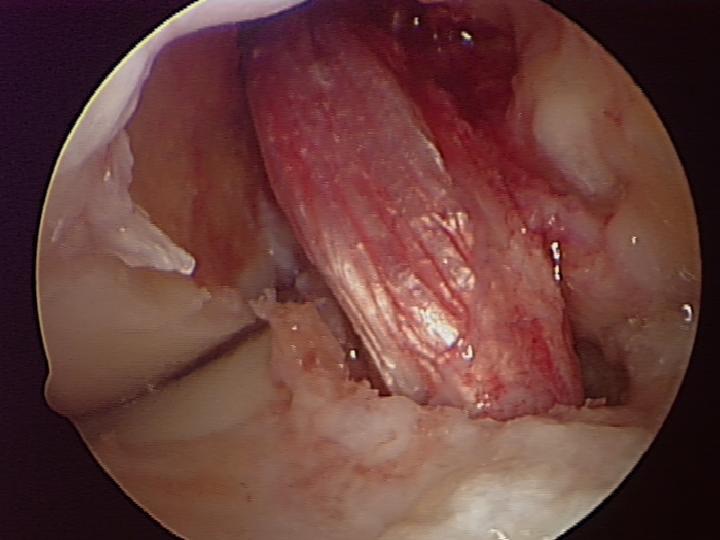

IMG_09332018-02-122018-02-12https://drlopezmartinez.com/wp-content/uploads/2019/12/logo-ok.pngTraumatólogo infantil y deportivo Dr López Martínezhttps://drlopezmartinez.com/wp-content/uploads/2019/12/logo-ok.png200px200px